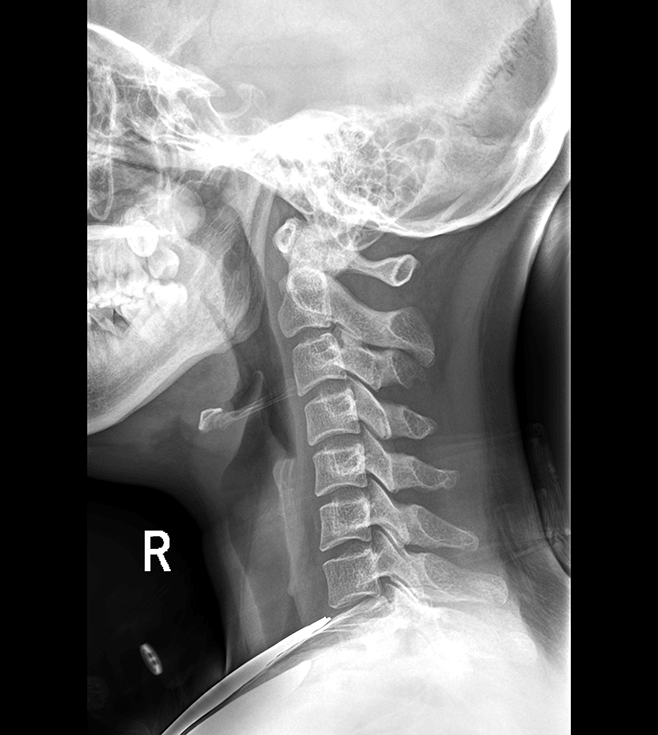

多功能诊断专用动态DR

太阳成集团tyc122cc入口科技全新设计的第四代床式动态DR,集拍片、透视、造影、全身拼接、尘肺体检于一体,一机多能,真正意义上实现全科室应用,提升医院实际效益。

多功能诊断应用专业设计

从医疗机构放射科的实际应用出发,针对多功能诊断进行多维度专业设计,优化病人检查体验,大幅提升操作技师工作效率。

高清动态平板探测器

搭载自主研发超清大视野动态平板探测器,600微米碘化铯大幅提升X线转化效率,独特的非晶硅阵列与高速读取集成电路紧密协作,轻松实现多帧率透视与高清点片。

专业的影像处理系统

“腾灵”系列搭载的IEAE影像处理系统,具备多项发明专利。本系统采用多频域图像处理技术,其6大核心处理模块使影像具有优秀的一致性、柔和性、空间层次感和纹理细腻度,为用户精准诊断病灶奠定了坚实的基础。